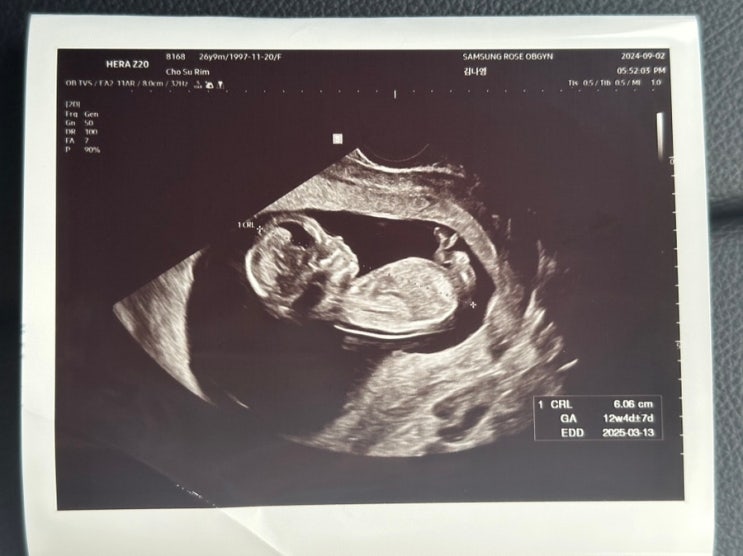

임신 13주 14주차 기록 (아들일까? 딸일까?)

13주 3일 처음 씩씩이의 존재를 알게된 날 6월 22일, 미국에 가기 전 몸무게를 쟀을 때는 분명 49kg였는데?...

씩씩이가 찾아와준 순간, 임밍아웃

24년 8월 어느날, 나지 않던 트러블이 이마에 너무 많이 나고, 생리도 안 하고, 기분도 왔다 갔다 하고, 식...